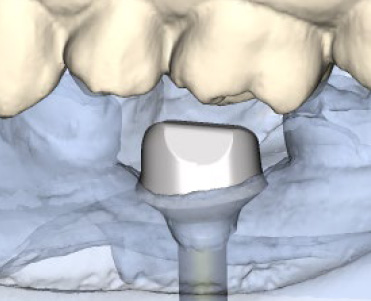

Atlantis

Dentsply Implant

Des piliers d'implants usinés avec profil d'émergence anatomique. Emplacement des implants en prévision de la restauration finale!